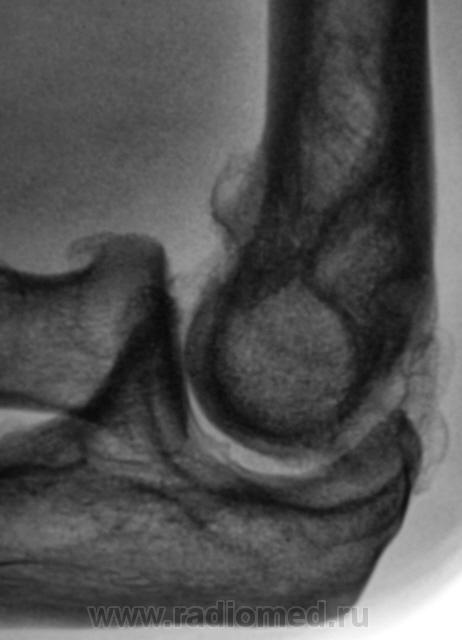

Пациент направлен на рентгенографию локтевого сустава. Была травма или не была не помнит. Пациент весьма пьющий, направлен хирургом с диагнозом "перелом". Рука в локтевом суставе полность не разгибается.

Ваше мнение уважаемые коллеги?

Наверно, застарелый перелом в области блока плечевой кости. Не понятен периостит.